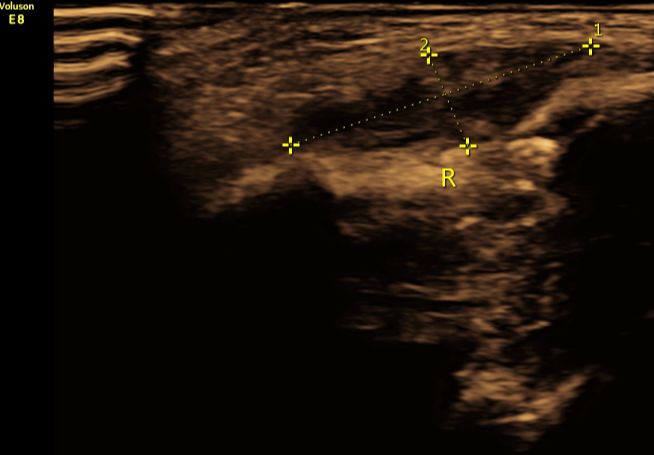

(图3:超声二维显示锁骨骨折周围血肿形成,呈不均质低回声。)

②合并周围软组织损伤:骨折周围可见血肿声像,呈不均质低回声。早期新鲜血肿时内部血流信号较丰富,晚期血流信号减少或消失;